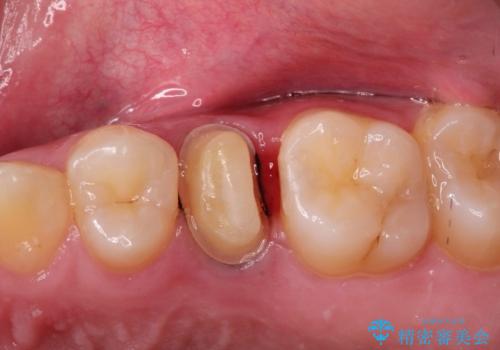

- 奥歯がズキズキ痛いことを主訴に来院されました。

根管治療を行なったのち、オールセラミッククラウンにて修復治療を行なっております。

根管治療を行なった歯は速やかに歯冠修復が必要です。